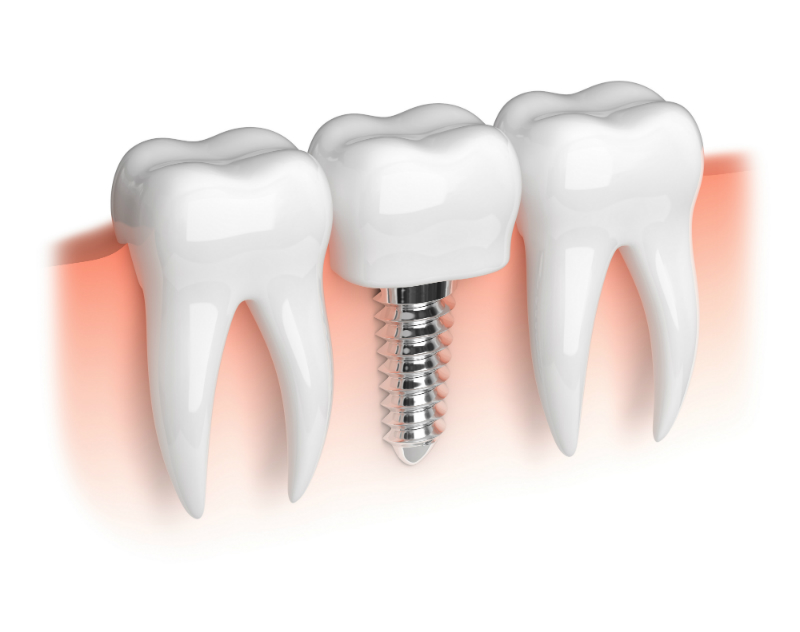

The benefits of dental implants range from enhanced oral functions to improved dental hygiene. Unlike bridges and dentures, dental implants can effortlessly be inserted in either your upper or lower jaw. Moreover, they are firm and fixed since they are surgically inserted into the bony ridges. Therefore, you do not have to worry about the movements or slipping of the implants while talking or eating. Discussed herein, are the numerous benefits of Dental Implants Mount Pleasant, SC.

How do dental implants enhance an individual’s oral function? Given that the mouth and jaws perceive implants are real teeth, you will be able to use your mouth normally. Once the implant has been surgically inserted into the jaw, the bone heals naturally around the implant thereby making it function like an actual tooth. Therefore, if you were unable to eat certain types of foods due to loss of chewing, you will enjoy a variety of foods ranging from nuts to apples.

Bone loss is one of the demerits of using bridges and dentures. But this is not the case with dental implants. Soon after the implant has been inserted, it will start to stimulate inactive bone tissues thus encouraging fresh growth as well as production. Sadly, if you have lost most of your bone density, you may not be a suitable candidate for Dental Implants Mount Pleasant, SC except if bone grafting is done.